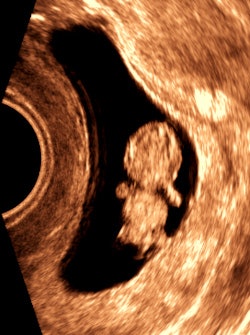

The clinic does not see pregnant women, but there were a few unexpected but very joyous first-trimester surprises (figure 4).